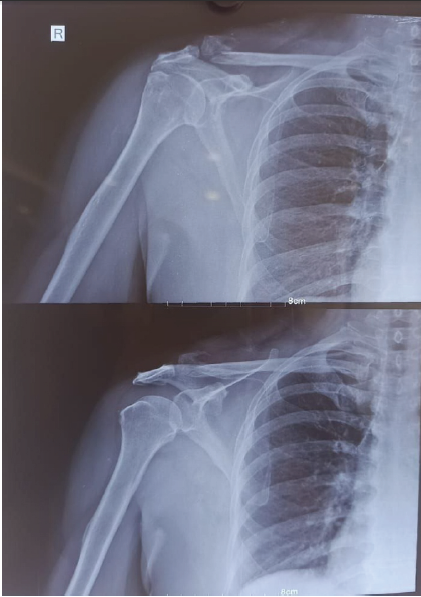

Clinical examination revealed gross swelling over the clavicle, tenderness along the right clavicle, and a restricted range of motion with no neurological deficit. Initially, thought of a lateral end clavicle fracture, stabilization was done by strapping, which aggravated the patient’s symptom and increased prominence over the medial end of the clavicle. Radiographic reassessment showed a medial and lateral end clavicle fracture [Fig. 2].

Figure 2: Pre-operative X-rays showing a bipolar clavicle fracture.